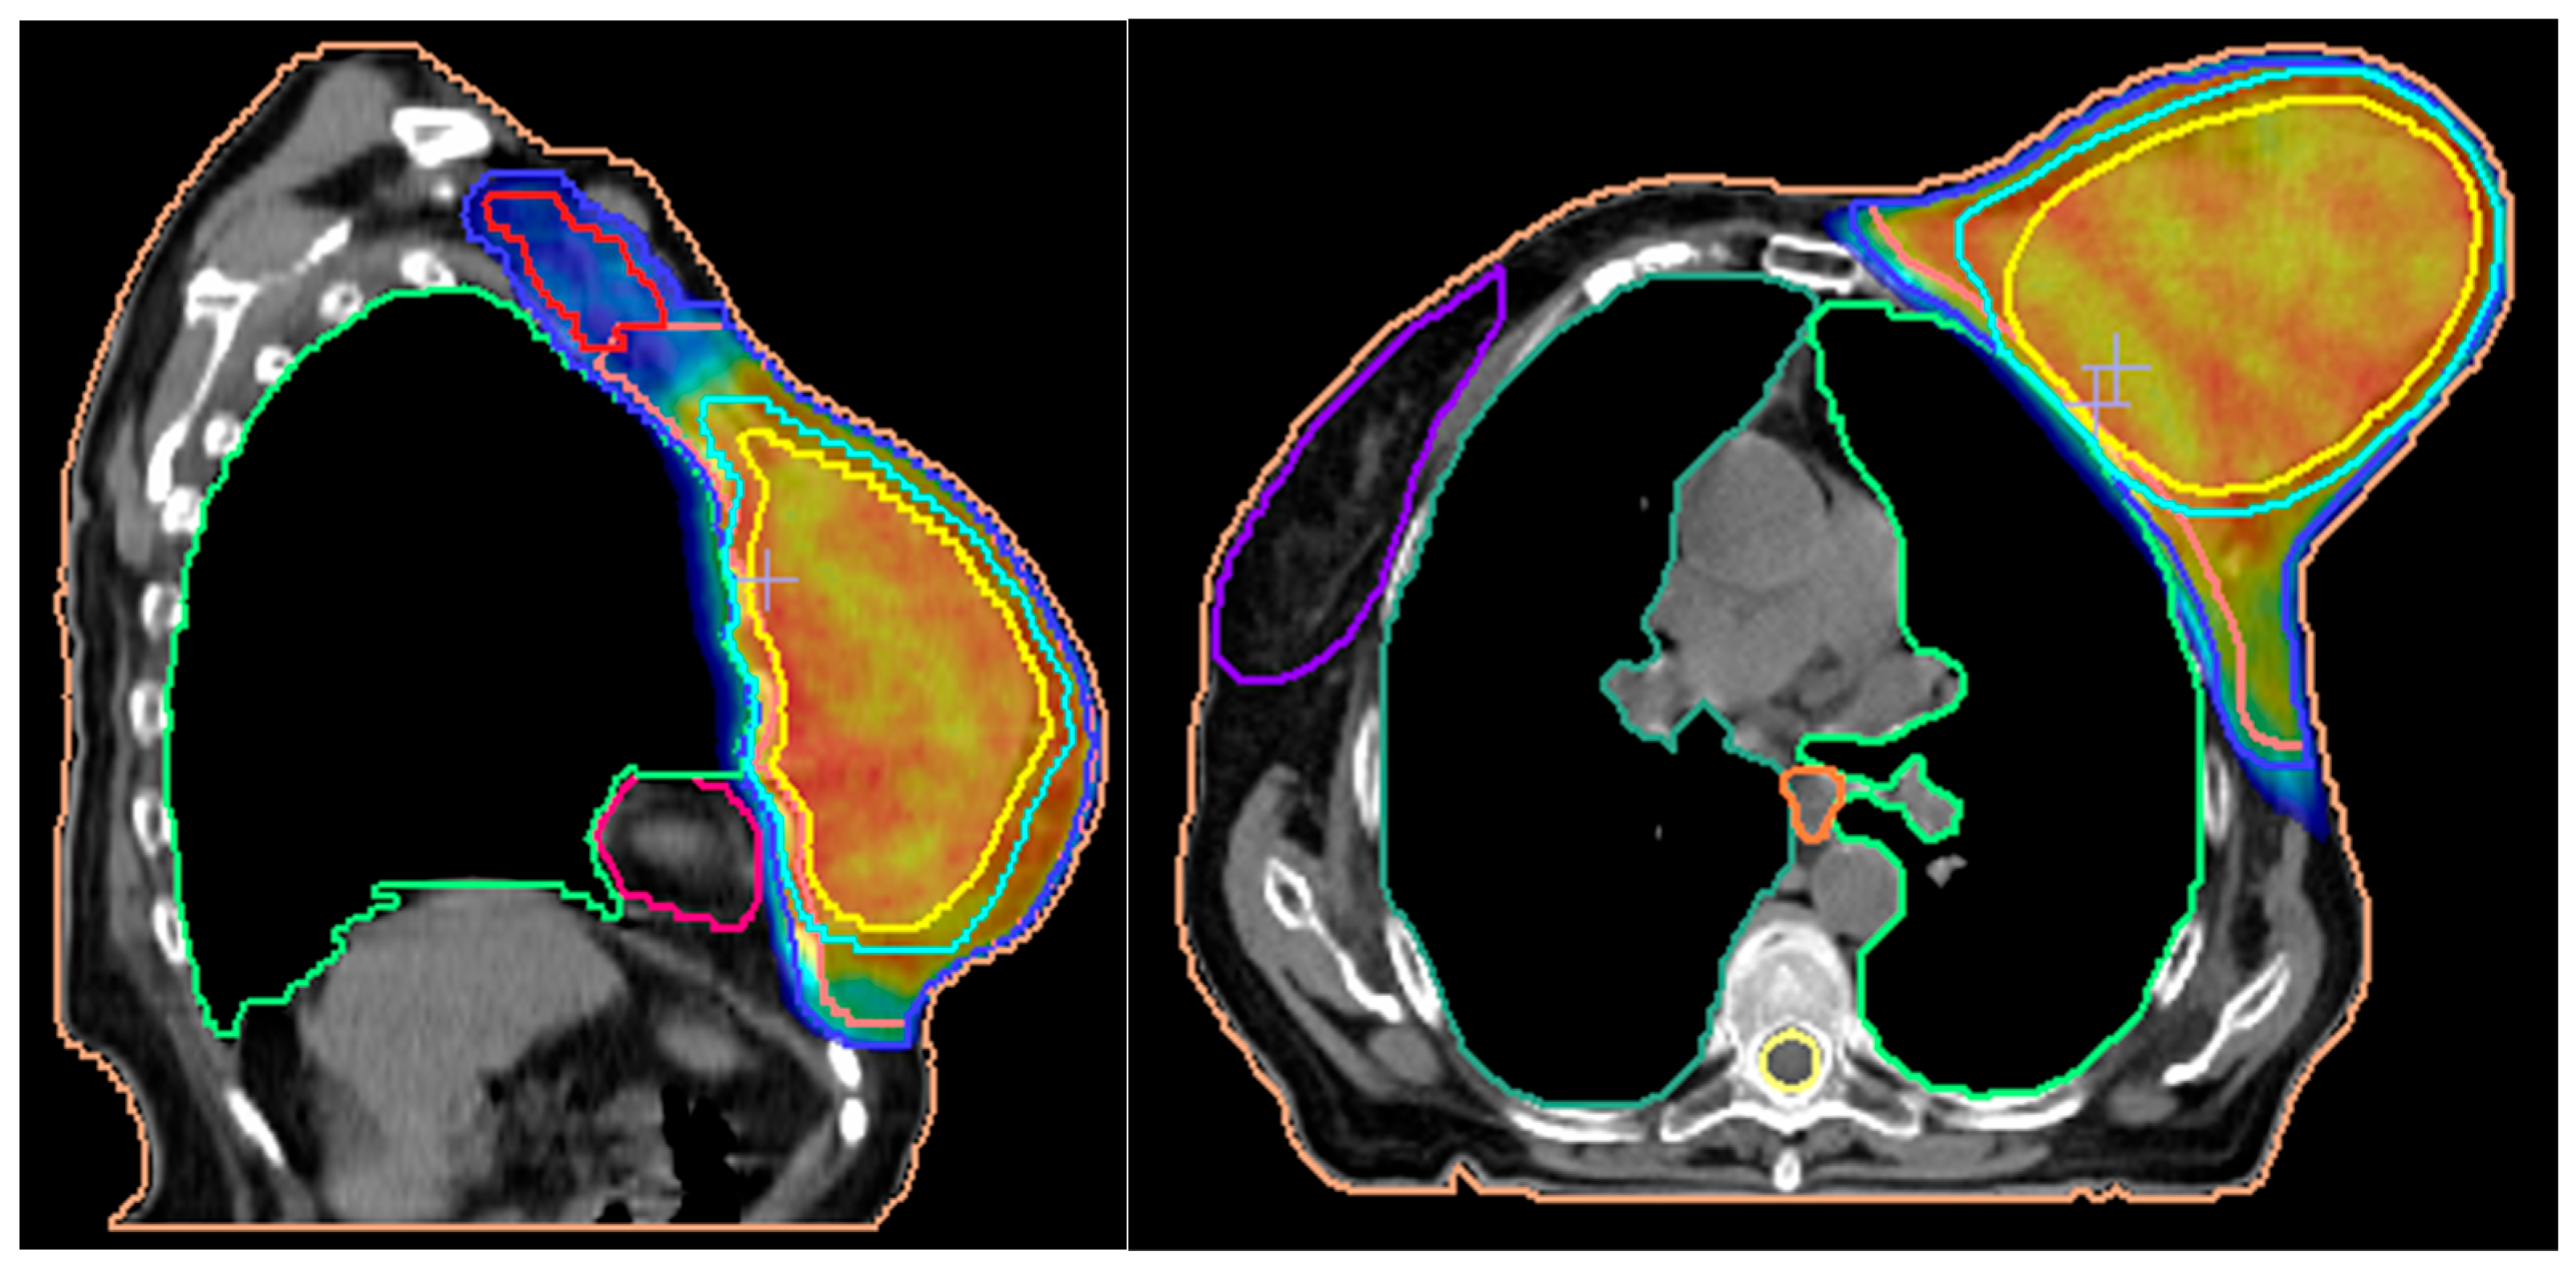

2. Case Report